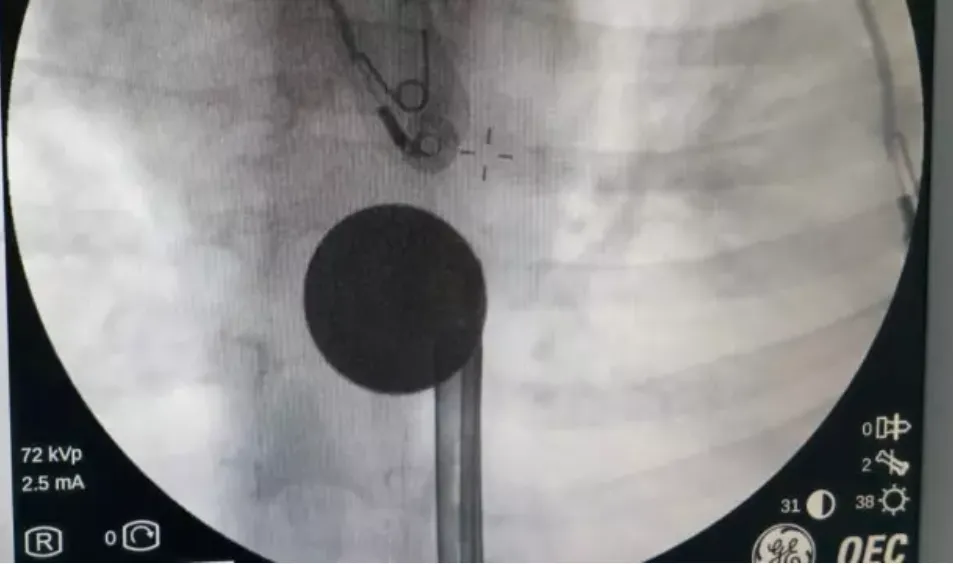

Y.K.'nın yemek borusuna kadar ilerlediği tespit edilen madeni para, gastroenteroloji uzmanı Dr. Yaren Dirik ve kulak burun boğaz hekimi Yasin Gökçınar tarafından müdahale edilerek çıkartıldı.

"Hastanemize başvuran 8 yaşındaki hastamızın yemek borusuna kaçan madeni para, gastroenteroloji ve KBB ekiplerimizin koordineli ve titiz çalışmasıyla herhangi bir komplikasyona yol açmadan başarılı bir şekilde çıkarılmıştır. Operasyon süreci sorunsuz geçmiş olup hastamızın genel durumu iyidir."